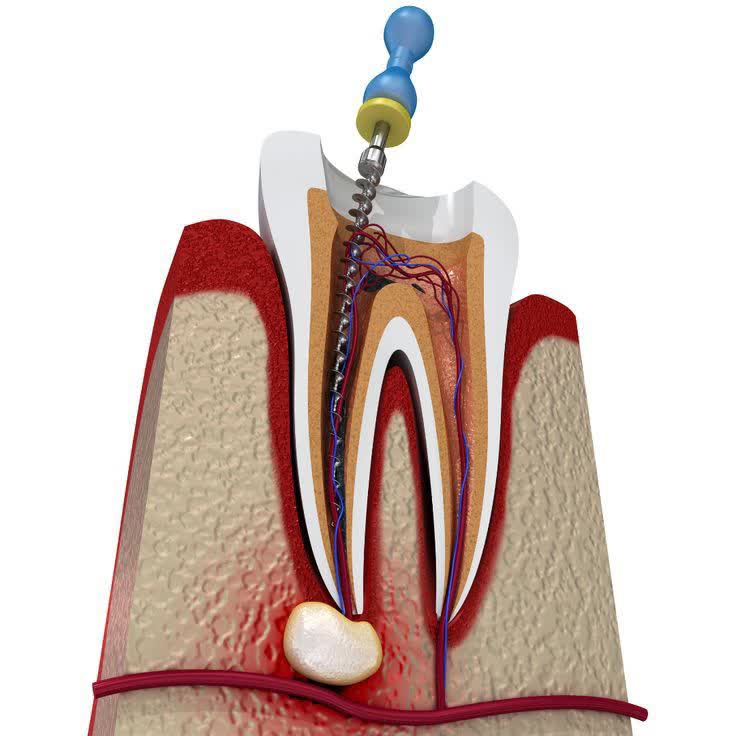

3- تهیه حفره برای دسترسی به پالپ (عصب دندان)

بعد از بی حس شدن کامل دندان، ابتدا پوسیدگی های تاج دندان حذف می شود و سپس راهی برای دسترسی به عصب دندان ایجاد می شود.

4- تمیز کردن کانال های ریشه

برای انجام عصب کشی دندان مورد نظر کانال های دندان تمیز می شوند و پس از آن فضای داخلی با مواد مخصوص پر می شود تا از نفوذ مجدد باکتری به داخل ریشه دندان جلوگیری شود.